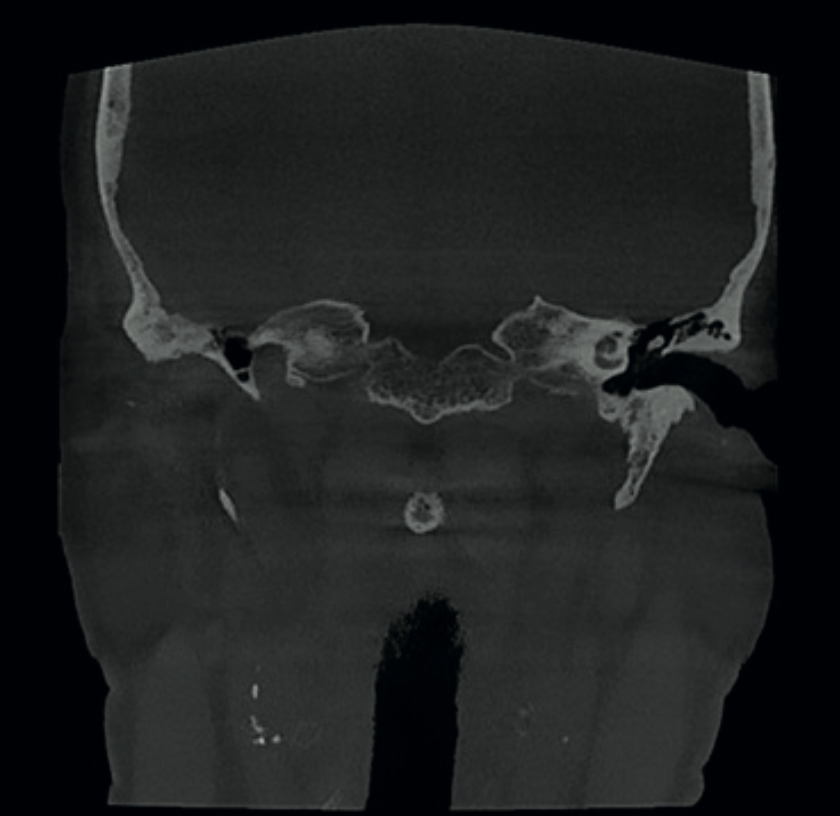

Critical finding 5 — Carotid artery calcifications

Calcified atheromatous plaques were identified at multiple locations along the carotid arteries — both in the neck and in the intracranial sections of the internal carotids. This is a significant finding that suggests advanced atherosclerosis and may indicate increased stroke risk.

Without early identification, carotid artery calcifications can progress silently. This patient required onward referral for Doppler ultrasound examination of the carotid arteries — a diagnostic step that would never have been triggered without thorough evaluation of the CBCT volume.

Coronal CBCT image showing bilateral calcifications in atheromatous plaques in the carotid arteries in the neck Axial CBCT image showing calcification in intracranial portions of the internal carotid arteries

Fig. 8 & 9 Left: bilateral calcified atheromatous plaques visible in the neck (coronal view). Right: calcification in the intracranial portions of the internal carotid arteries (axial view).